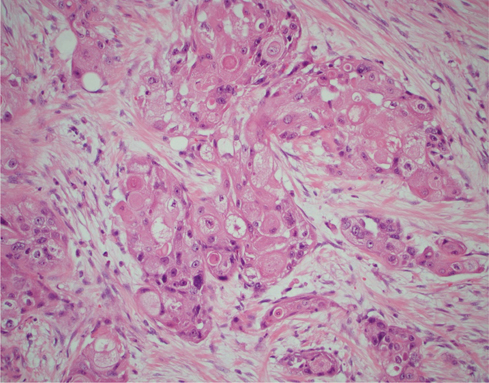

He was referred to a urology team on the suspicion of urothelial carcinoma. The urology team performed right-sided cystoscopy and retrograde pyelogram with lavage cytology which demonstrated a normal collecting system and normal urothelial cells which made the differential diagnosis of urothelial malignancy unlikely. The differential diagnosis included renal cell carcinoma (RCC). He had no haematuria; urine microscopy, culture and sensitivity were normal, and there were no other urological symptoms. The opinion of the interventional radiologist was that a percutaneous biopsy of the mass was too risky given its proximity to major vasculature structures. The patient underwent a positron emission tomography–magnetic resonance imaging (PET-MRI) scan that demonstrated a right-sided renal hilar mass encasing the renal vessels and showed evidence of invasion into the inferior vena cava (IVC) with possible invasion of the right crus of the diaphragm. No metastatic lesions were detected at other sites (Figure 1).

Fig 1

Figure 1. Coronal PET-MRI scan demonstrating a solitary enhancing lesion in the right renal hilum (arrow).